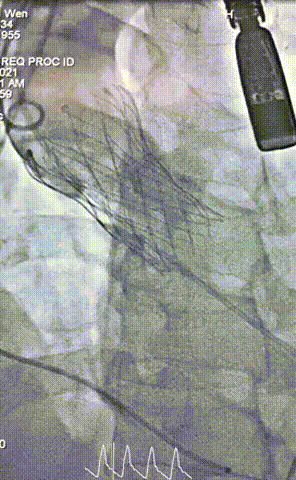

7.瓣膜形态良好,未见明显形态改变,遂予以完全释放;

8.即时超声评估提示存在少量瓣周漏,峰值跨瓣压差约10mmHg经术中讨论认为瓣上限制性结构压缩为瓣周漏主因,遂予以球囊后扩;

9.后扩完毕,造影示微量瓣周漏,瓣膜形态良好,手术圆满成功!